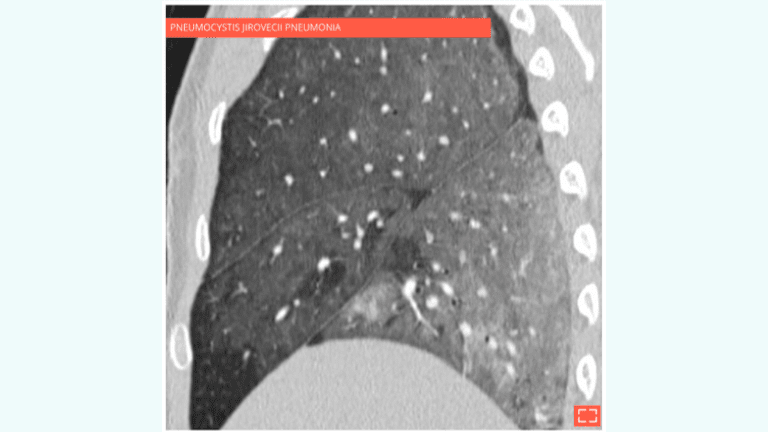

2. Diffuse ground-glass opacity

Diffuse ground-glass opacity

Diffuse ground-glass opacity of the lung sparing subpleural areas.